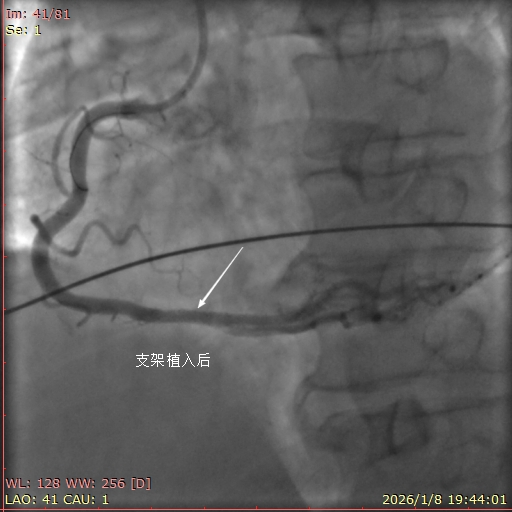

1月8日,17点40分患者潘某,男,51岁,江苏省人,因公来平度市新河化工园区出差,突发胸痛30分钟,就诊于当地胸痛救治单元,救治单元值班医师第一时间识别患者为高危胸痛,初步诊断为急性ST段抬高型心肌梗死,立即联系平度市第三人民医院胸痛中心,呼叫120,负荷量双联抗血小板聚集药物,吸氧,监护。急救中心接到呼叫后,立即出车。期间当地值班医师,患者的同事,领导都鼓励患者树立战胜疾病的信心!患者亲人未在身边,汇报给李丽院长助理,要求绿色通道,全力救治病人。院内导管室启动并激活。患者到达医院后绕行急诊和CCU直达导管室。冠脉造影提示右冠远段斑块破溃,99%狭窄,植入支架一枚,完全血运重建。胸痛救治单元与胸痛中心接力救治病人,无缝衔接,挽救了患者的生命,得到了患者及家人,同事,领导的赞许。(鲁网记者)